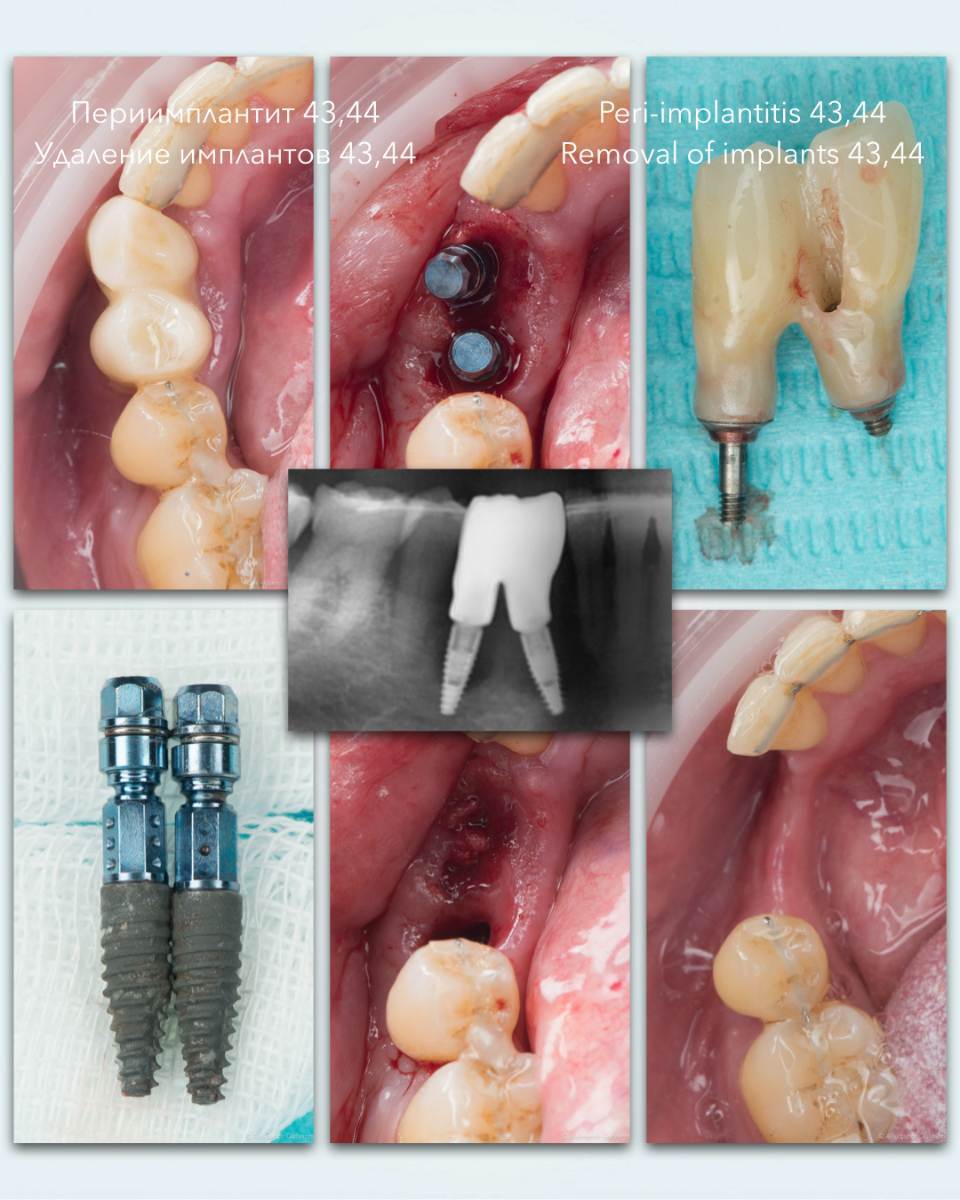

stommm Опубликовано 28 сентября, 2024 Поделиться Опубликовано 28 сентября, 2024 Всем доброго времени суток. История длиною в 2 года 9 месяцев. Ортопед Залим Иругов, техник Виталий Шамин. Приятного просмотра) 10 1 1 Ссылка на комментарий